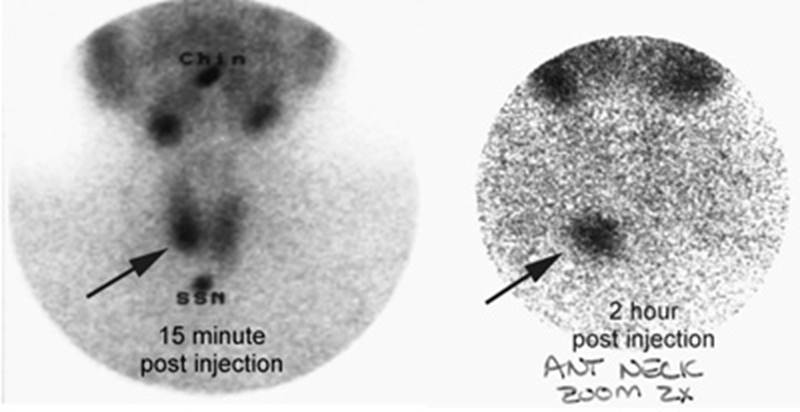

Figure 19 - Lingual thyroid

Figure 20 - Presented with symptoms of

hyperthyroidism. The

T4 level was elevated and the scan was done to exclude

Graves disease. The Tc-99m

pertechnetate exam demonstrated

no evidence of tracer accumulation in the neck consistent with subacute

thyroidit